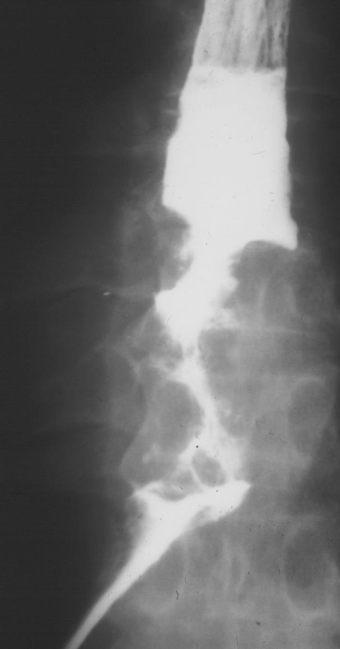

Rugger jersey spine’ (renal osteodystrophy

Bamboo spine | Ankylosing spondylitis

A. Give the name of the used imaging modality. B. What name is given to this appearance of the spine?